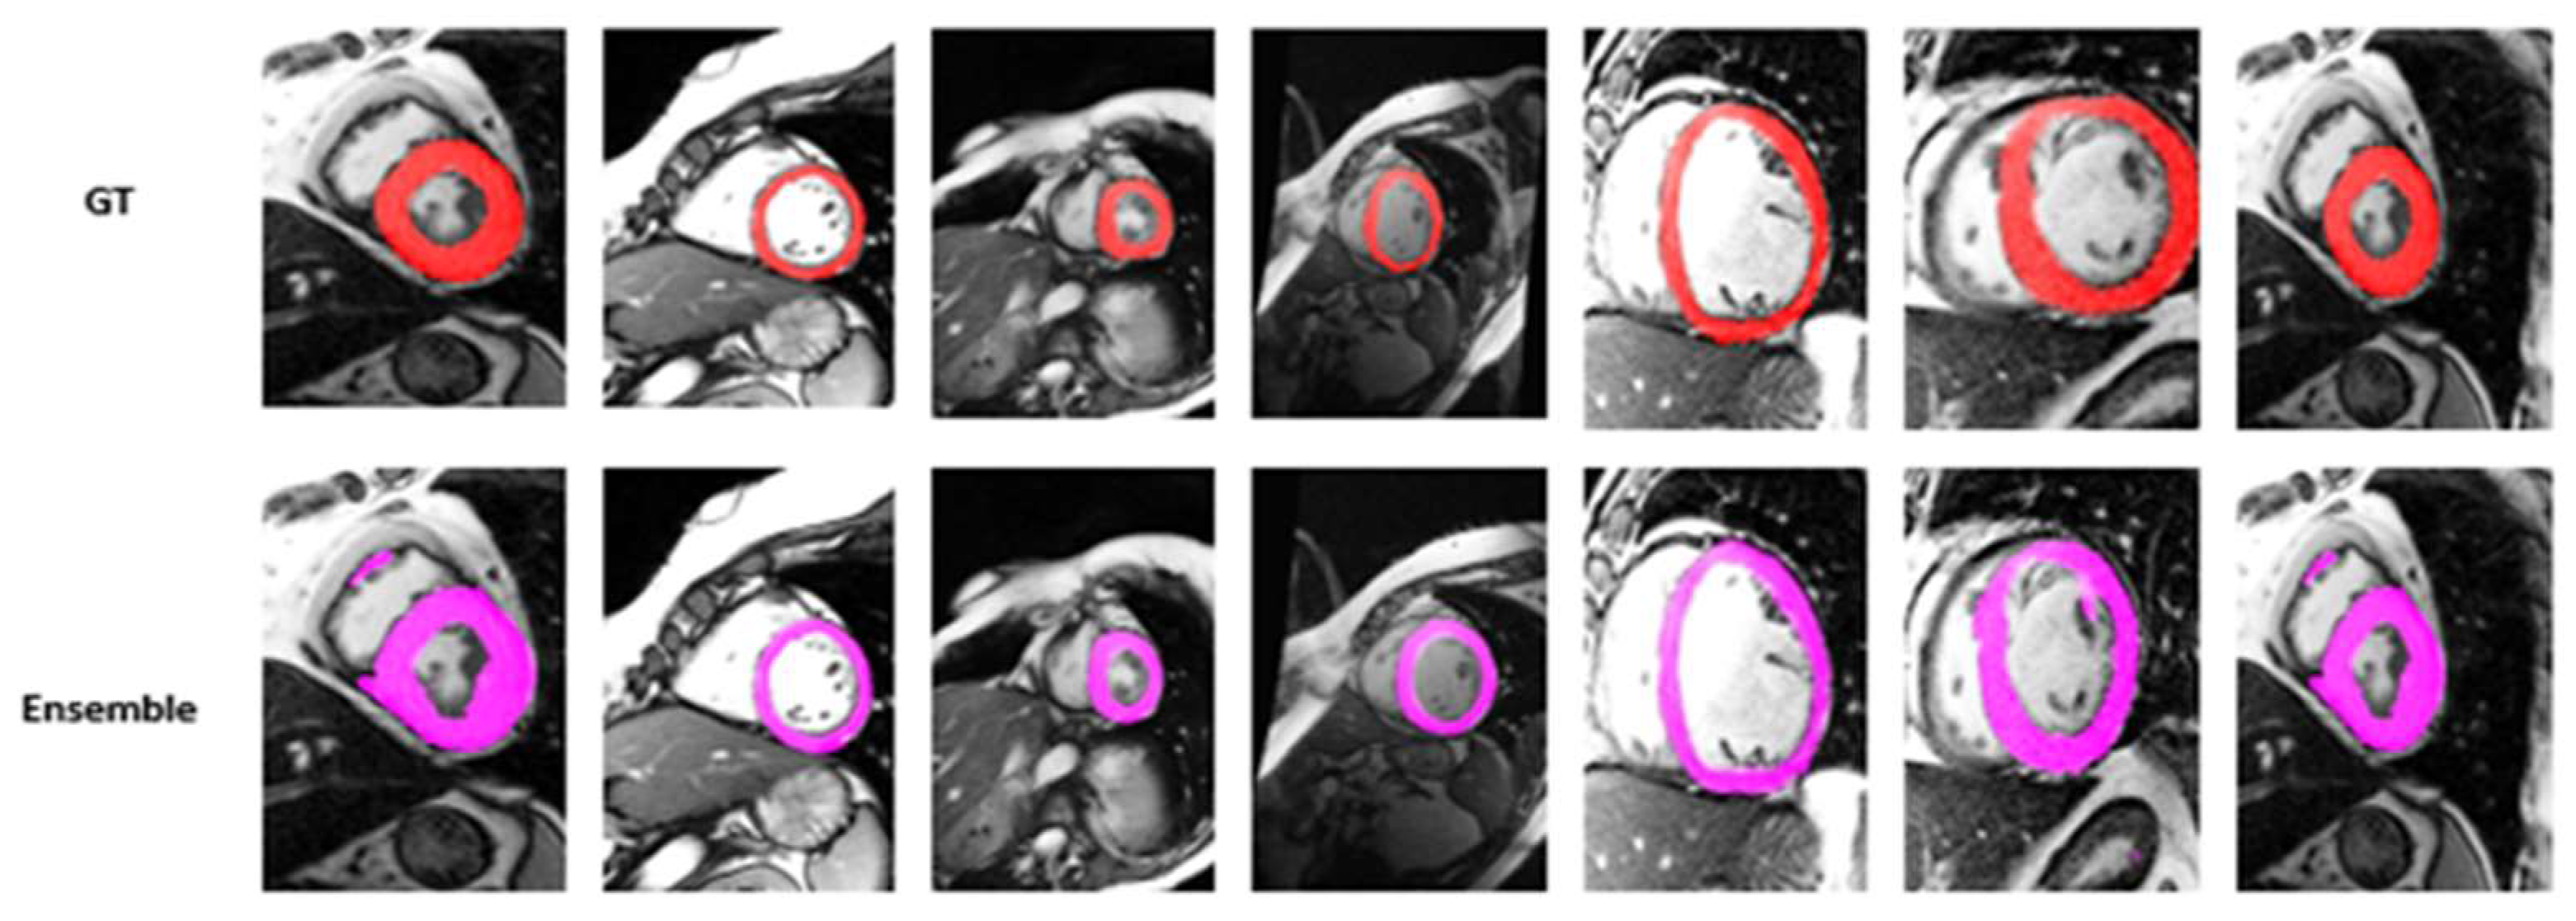

4.2. Visualization Segmentation Results

| Ensemble Model | 84.99 | 75.17 | 5.6782 | 12.6781 | 97.99 | 90.78 | 0.2790 | 1.8932 | 0.0674 |